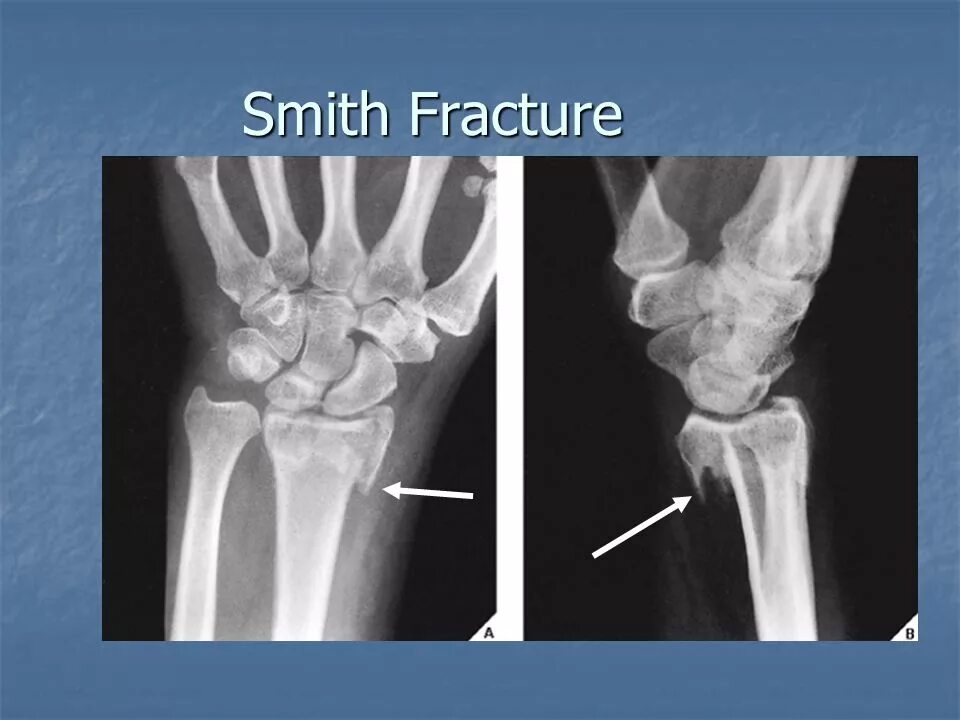

Перелом смита